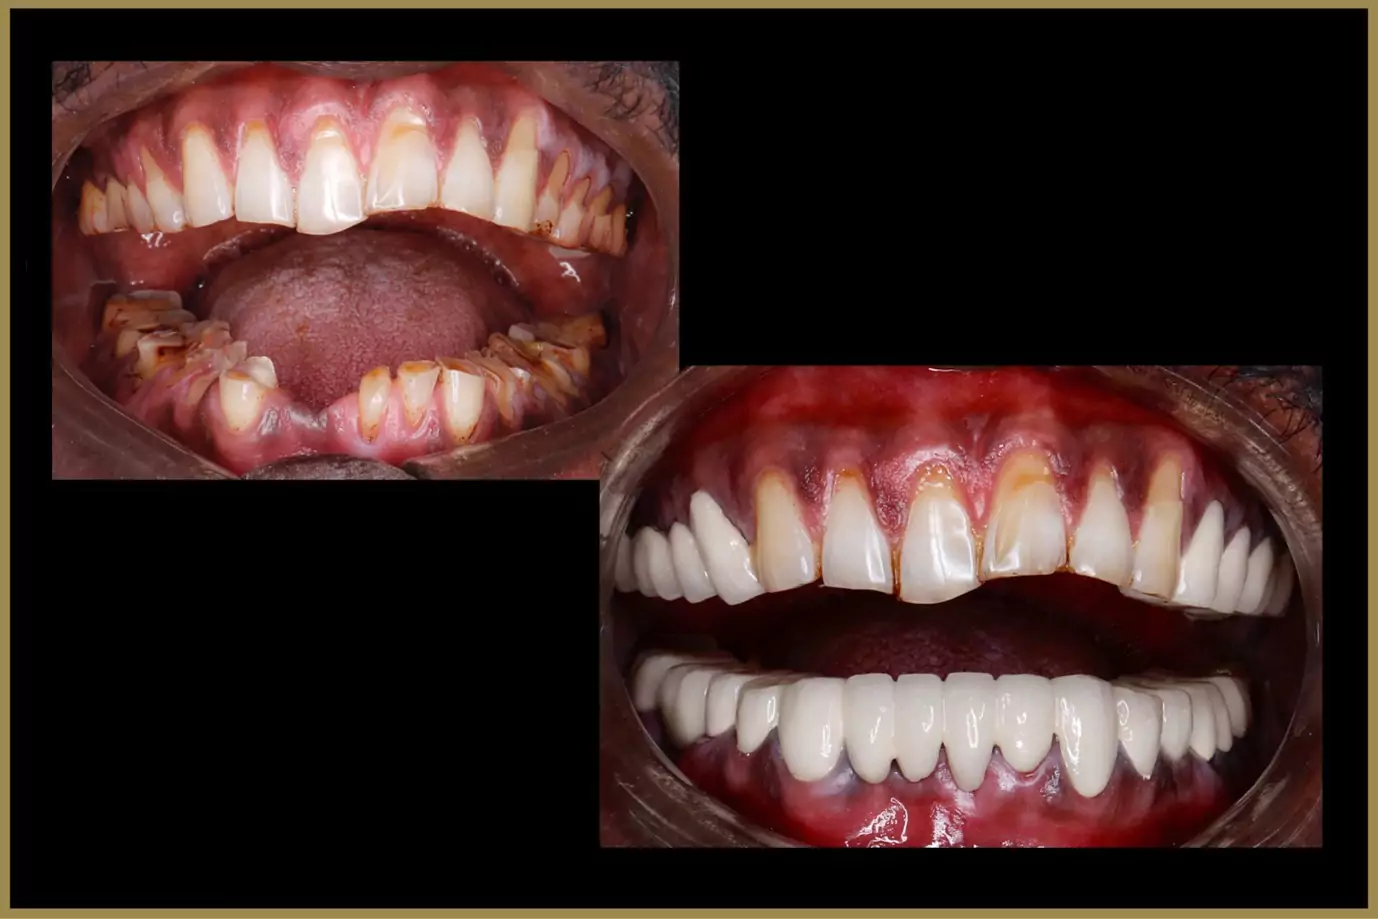

From preventive care to orthodontics, implants, cosmetic dentistry, and digital treatments.

Digital X-rays, intraoral scanning, smile simulations, and computer-guided treatment planning.